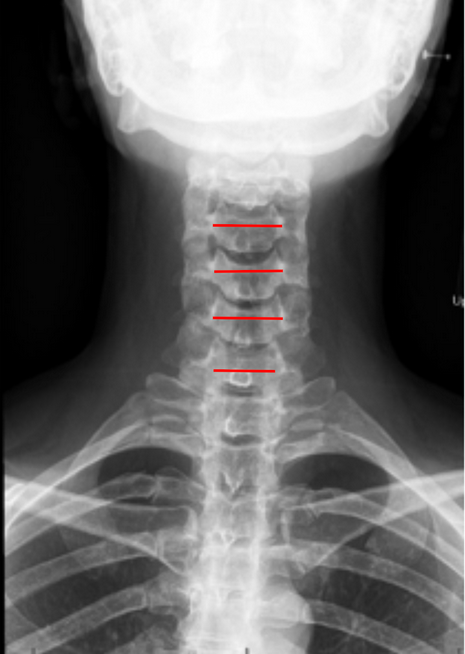

The Interpedicular Distance (IPD) is a radiographic measurement used to assess the transverse (mediolateral) width of the spinal canal at a given vertebral level. It represents the horizontal distance between the medial borders of the pedicles on an anteroposterior (AP) cervical spine X-ray.

• Obtain a well-centered AP cervical spine X-ray (as shown in the provided images).

• Identify the pedicles on both sides of the vertebra at the level of interest.

• The pedicles appear as oval or circular cortical rings in the lateral aspect of the vertebral body shadows.

• Draw vertical reference lines along the medial cortical margins of each pedicle.

• Measure the shortest horizontal distance between the two lines — this is the Interpedicular Distance (IPD) for that level.

• Repeat at multiple levels (C3–C7) and record the narrowest measurement, which represents the level most at risk for canal stenosis.